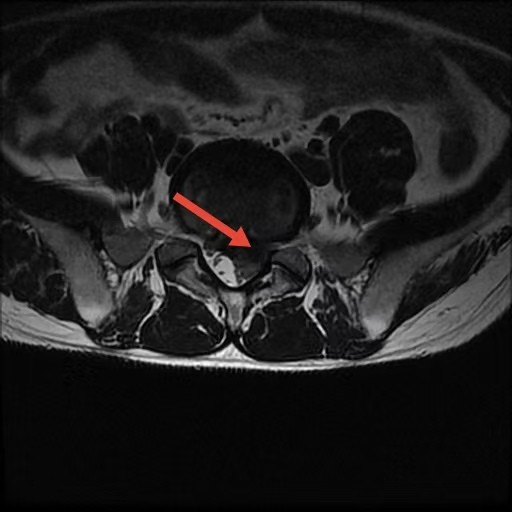

術前

術后